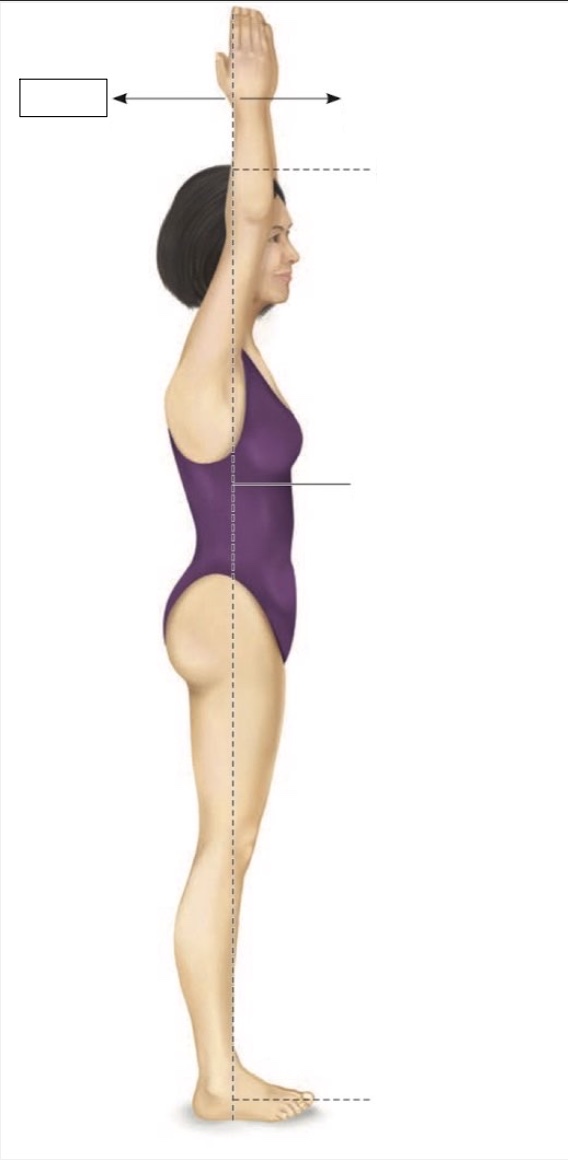

Superior

Midline

Midaxillary

Torso